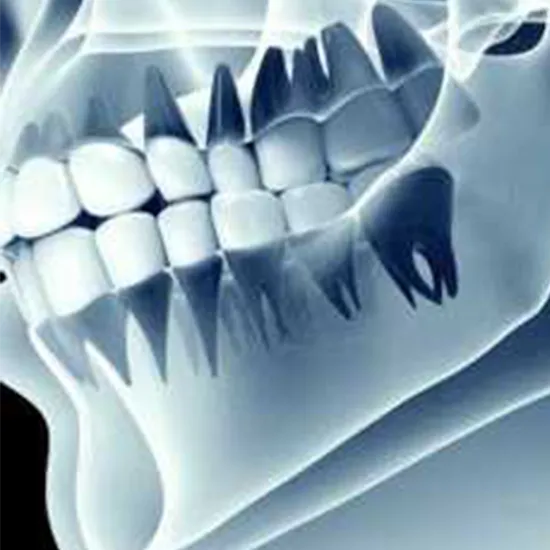

Orthopantomogram (OPG) X-rays are routinely used as two-dimensional panoramic dental X-rays in dental practice. An OPG X-ray captures the teeth, jawbones, and surrounding tissues using a single film.

It exposes the quantity, location, and development of all teeth, even those that have fractured or have not yet erupted. This test assists dentists in identifying a variety of problems, including sinusitis, tooth decay, jaw tumors, and oral cancer.

The result shows the teeth, jaws and surrounding structures in detail that allows the doctor to evaluate the cavities, gum diseases,jaws, tumours, sinus and other disorders.